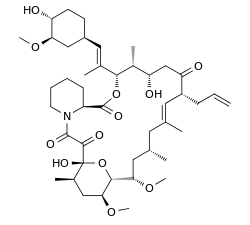

Chemically, it is a macrolide lactone[8] that was first discovered in 1987, from the fermentation broth of a Japanese soil sample that contained the bacterium Streptomyces tsukubensis.

The biosynthesis of tacrolimus is hybrid synthesis of both type 1 polyketide synthases (PKS 1) and nonribosomal peptide syntheses (NRPS). The research shows the hybrid synthesis consists of ten modules of type 1 polyketide synthase and one module of nonribosomal peptide synthase. The synthetic enzymes for tacrolimus are found in 19 gene clusters named fkb. The 19 genes are fkbQ, fkbN, fkbM, fkbD, fkbA, fkbP, fkbO, fkbB, fkbC, fkbL, fkbK, fkbJ, fkbI, fkbH, fkbG, allD, allR, allK and allA.[53]

There are several possible ways of biosynthesis of tacrolimus. The fundamental units for biosynthesis are following: one molecule of 4,5-dihydroxycyclohex-1-enecarboxylic acid (DHCHC) as a starter unit, four molecules of malonyl-CoA, five molecules of methylmalonyl-CoA, one molecule of allylmalonyl-CoA as elongation units. However, two molecules of malonyl-CoA are able to be replaced by two molecules of methoxymalonyl CoA. Once two malonyl-CoA molecules are replaced, post-synthase tailoring steps are no longer required where two methoxymalonyl CoA molecules are substituted. The biosynthesis of methoxymalonyl CoA to Acyl Carrier protein is proceeded by five enzymes (fkbG, fkbH, fkbI, fkbJ, and fkbK). Allylmalonyl-CoA is also able to be replaced by propionylmalonyl-CoA.[53]

The starter unit, DHCHC from the chorismic acid is formed by fkbO enzyme and loaded onto CoA-ligase domain (CoL). Then, it proceeds to NADPH dependent reduction(ER). Three enzymes, fkbA,B,C enforce processes from the loading module to the module 10, the last step of PKS 1. fkbB enzyme is responsible of allylmalonyl-CoA synthesis or possibly propionylmalonyl-CoA at C21, which it is an unusual step of general PKS 1. As mentioned, if two methoxymalonyl CoA molecules are substituted for two malonyl-CoA molecules, they will take place in module 7 and 8 (C13 and C15), and fkbA enzyme will enforce this process. After the last step (module 10) of PKS 1, one molecule of L-pipecolic acid formed from L-lysine and catalyzed through fkbL enzyme synthesizes with the molecule from the module 10. The process of L-pipecolic acid synthesis is NRPS enforced by fkbP enzyme. After synthesizing the entire subunits, the molecule is cyclized. After the cyclization, the pre-tacrolimus molecule goes through the post-synthase tailoring steps such as oxidation and S-adenosyl methionine. Particularly fkbM enzyme is responsible of alcohol methylation targeting the alcohol of DHCHC starter unit (Carbon number 31 depicted in brown), and fkbD enzyme is responsible of C9 (depicted in green). After these tailoring steps, the tacrolimus molecule becomes biologically active.[53][54][55]